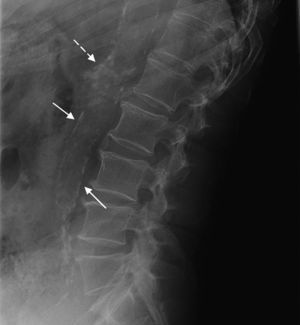

Study technique and evaluation of variablesAccording to the AAC-24 scale, in the lateral lumbar spine X-rays, the aorta anterior and posterior walls were divided into four segments corresponding to the area located in front of vertebrae L1–L4. The segments evaluated were those between an imaginary line parallel to the surface of vertebral bodies and between them. Based on this scale, aortic calcification was scored as 0 (no calcification), 1 (calcification in one third or less of the aortic wall), 2 (calcification in more than one third, but in two thirds or less of the aortic wall) or 3 (calcification of more than two thirds of the aortic wall). It was estimated that there was aortic calcification when images of calcic density were observed in an area anterior and parallel to the lumbar spine, which could appear as diffused white dots, as a linear image of calcification of the anterior and/or posterior aortic wall or as a circumferential image, homogeneous or not, of calcic density. After the sum of both walls, the total score was between 0 and 24 (Fig. 1). At the initial stage of the study, the evaluators received a specific training in the use of the AAC-24 scale and the application of the Kiel et al. radiographic atlas,27 under the supervision of one of the authors (RLA), a radiologist with 18 years of clinical experience. To this end, they all evaluated 10 X-rays with different degrees of aortic calcification, which were later ruled out for analysis.

Lateral lumbar spine simple X-ray with images of calcifications in the abdominal aorta of one participant in the study. The partial scores in the ACC-24 scale (anterior wall+posterior wall) were: Level L1=1 (1+0), level L2=0, level L3=4 (3+1), level L4=2 (0+2) that is an overall score of 7.